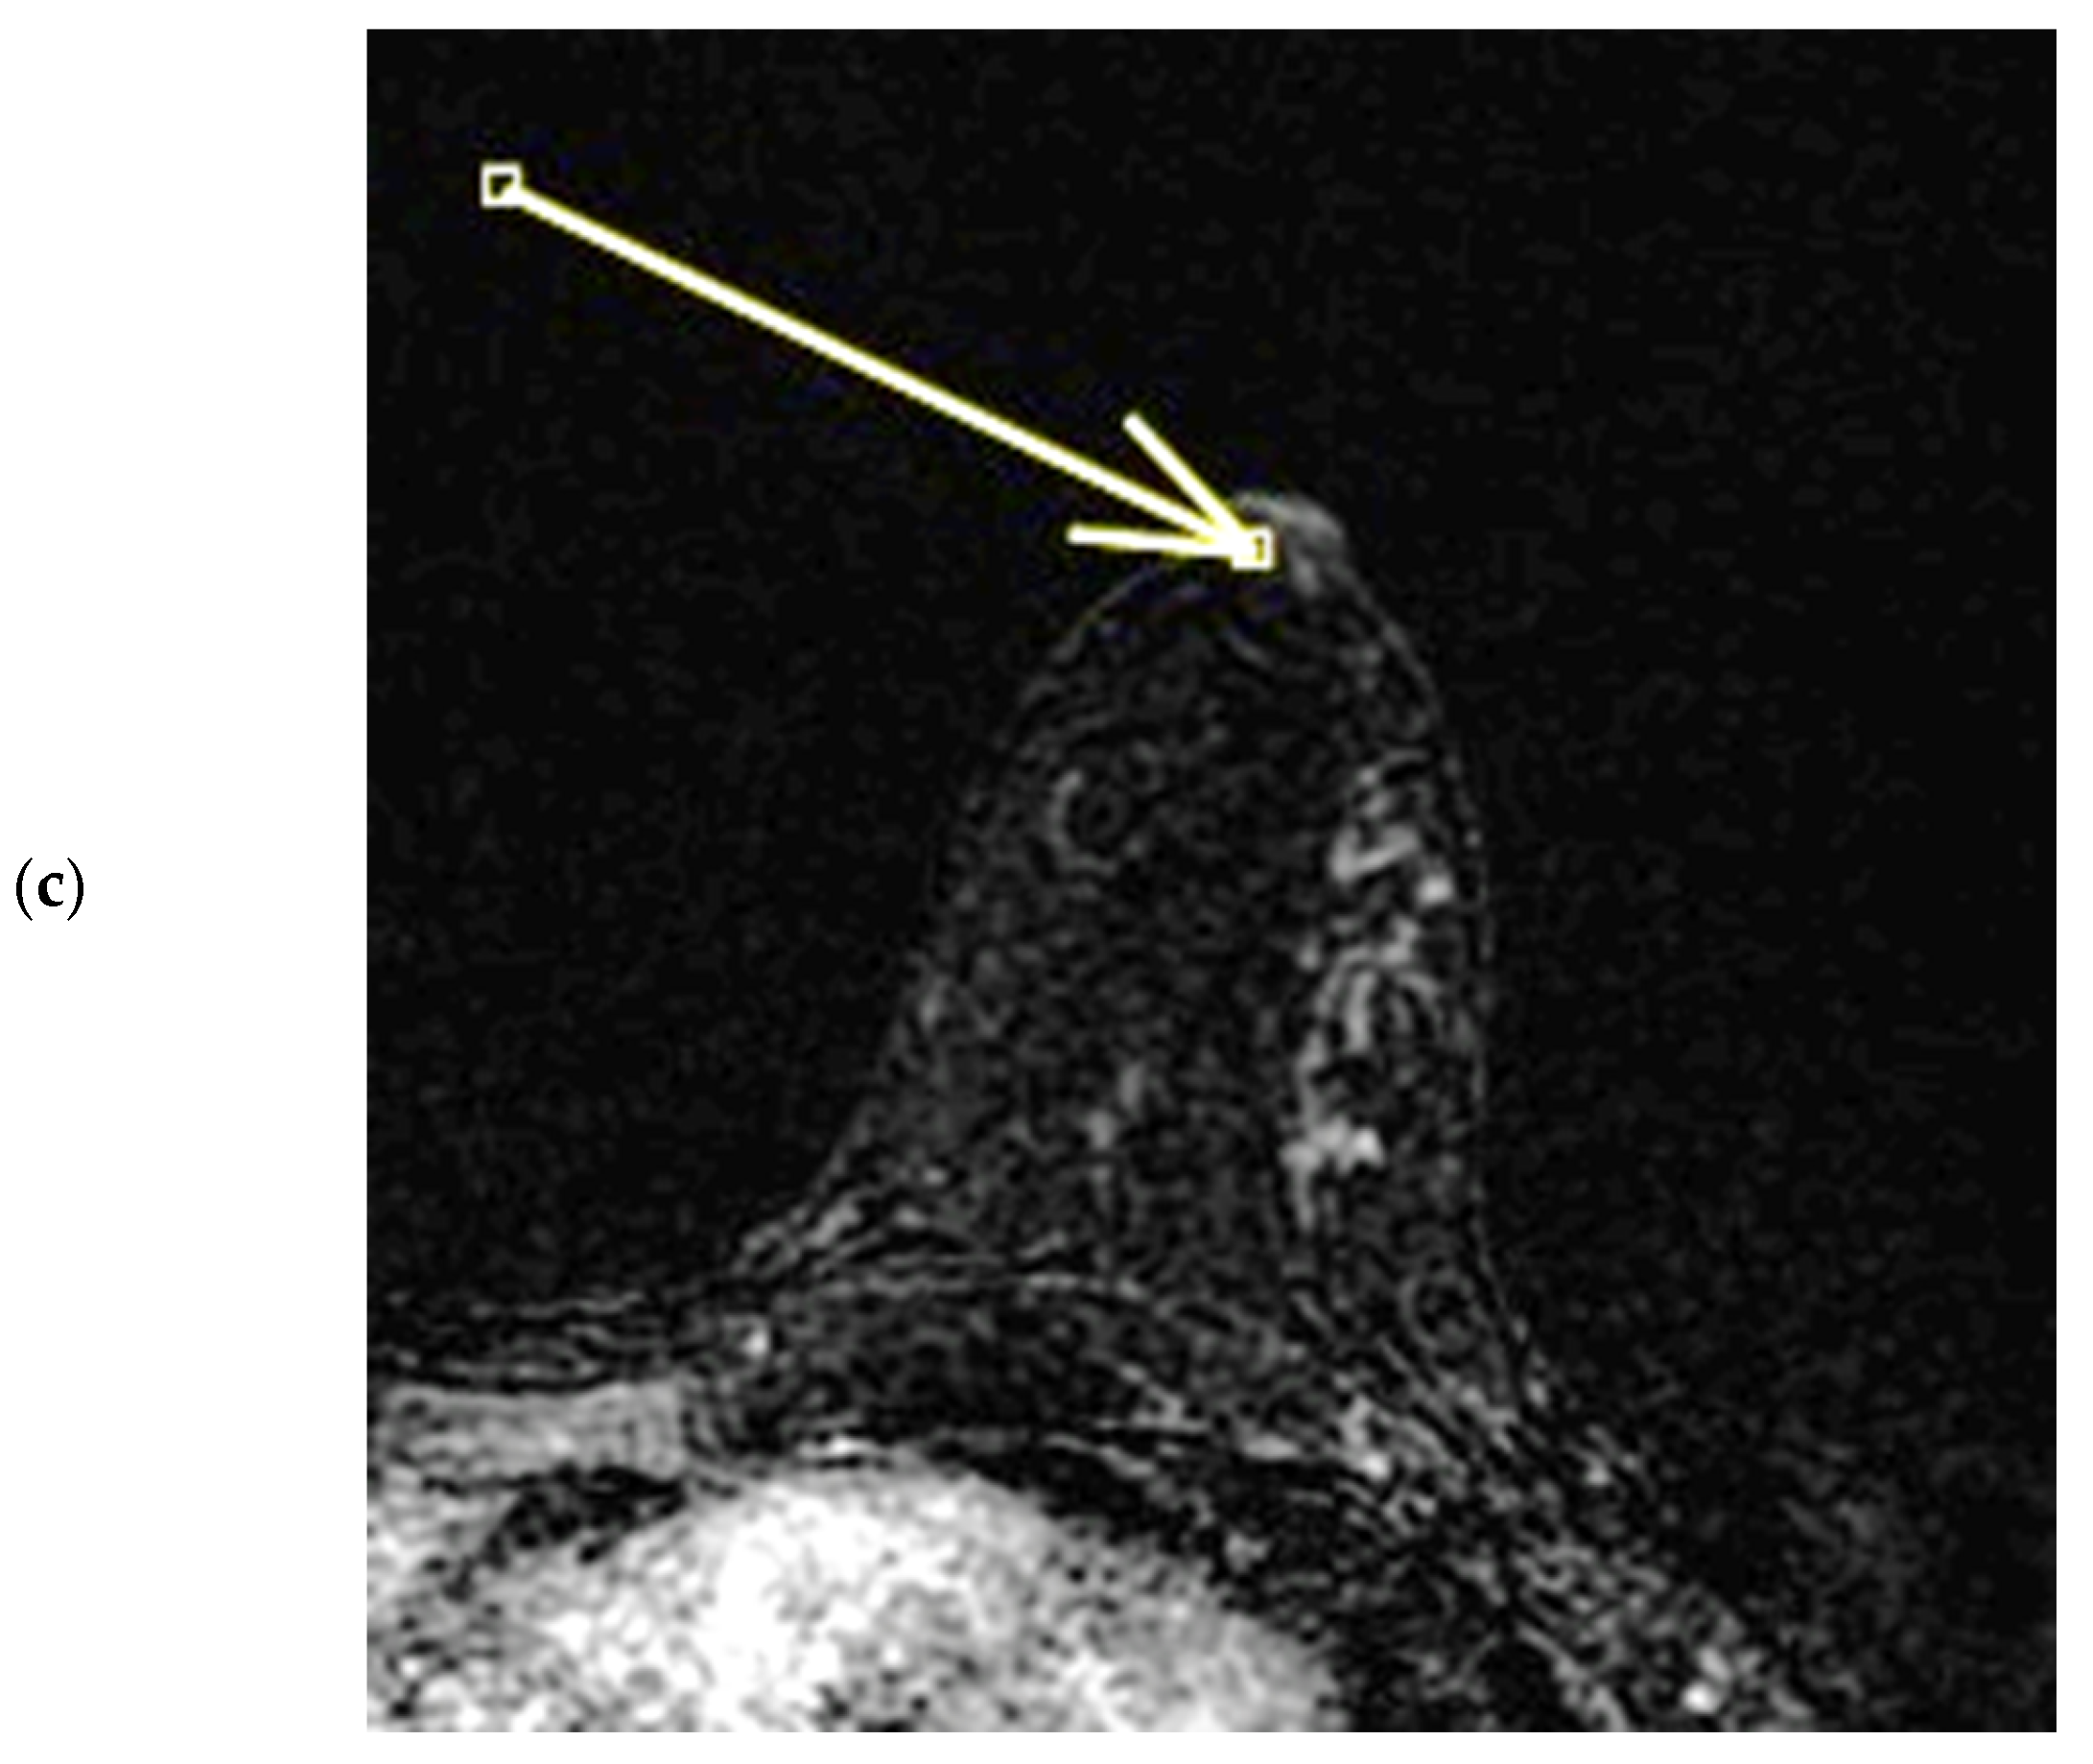

Figure 7.

(a–c) Patient’s name M.E. In the post-contrast fat-suppressed T1 sequences and in the MIP (maximum intensity projection) reconstruction of the first post-contrast fat-suppressed T1 sequence, we notice a gross area of pathological enhancement which affects the external quadrants of the left breast and infiltrates the nipple, without retraction (a,b). During ce-MR, SLE and NEZ enhancement patterns are present; the arrow indicates mild linear INE of the left breast nipple (c).

Figure 8.

(a,b) Patient’s name M.E. The ce-CT scan shows enhancement of the base of the left nipple alone (no body; arrow). Morphology of the nipple is everted.